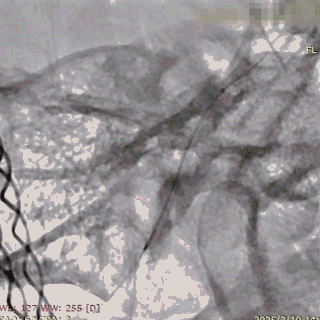

支架及支架微导管到位。

支架头端打开。

支架远端打开造影。

等张释放,支架中段打开至50%释放标记点。

支架中段打开造影。

支架近端打开,完全释放。

支架完全释放造影。

术后即刻造影。